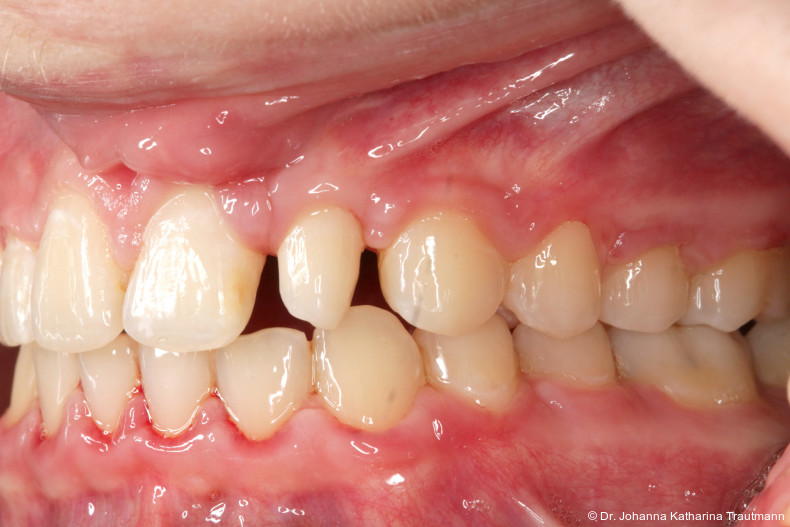

Nach transversaler Nachentwicklung der Maxilla mittels GNE nach Veltri wurde der Zahn 23 geschlossen freigelegt und an einem individualisier ten TPA nach distal angebunden. Zur Aufrichtung der Front und Mesialisierung des hypoplastischen Zahnes 22 kam zusätzlich eine 2x3Mechanik zum Einsatz. Eine rein translatorische Bewegung eines Zahnes ist auch mit einer festsitzenden Apparatur schwer zu erreichen, da der Kraftansatzpunkt nicht identisch mit dem Widerstandszentrum des Zahnes ist.7 Diese Problematik kann einerseits durch das Einbringen eines Versetzungsmomentes adressiert werden, andererseits durch eine Verlagerung des Kraftansatzpunktes. Angelehnt an den von Hong et al. beschriebenen Power Arm 8 wurde hierfür palatinal an Zahn 22 ein cranial gerichteter Hook angebracht (Abb. 3). Da Zahn 22 aufgrund seiner Hypoplasie eine verkürzte Wurzel aufwies, konnte so die Distanz zwischen Widerstandszentrum und Kraftangriffspunkt effizient reduziert werden. Eine weitere biomechanische Schwierigkeit stellte das geringe Alveolarknochenangebot im Spalt bereich mesial von 22 dar. In Bereichen mit Knochendefizit verschiebt sich das Widerstandszentrum nach apikal und wie in diesem Fall zusätzlich nach distal.9, 10 Um dem erhöhten Risiko für Kipp bewegungen entgegenzuwirken, muss hier besonders auf die Steuerung des M/F-Quotienten geachtet werden. Der vestibulär durchgebrochene Zahn 13 benötigte keine Freilegung. Um seine korrekte Einstellung zu ermöglichen, wurde die Mesialwanderung des Zahnes 16 mithilfe des TPAs korrigiert sowie eine Mittellinienkorrektur nach links mittels 2x3 Mechanik durchgeführt.

Im Rahmen der Multibrackettherapie wurde bewusst der Zahn 13 aus dem Hauptnivellie rungsbogen ausgelassen, um Kippungen und Asymmetrien im Zahnbogen zu vermeiden. Der Zahn 23 wurde locker mit einer Distanz ligatur angebunden, um eine weitere Bewegung nach vestibulär zu erreichen. Auf einem 0.019" x 0.025" Stahlbogen erfolgte anschlie ßend mittels Umgehungsbiegung sowie eines Overlaybogens (0.014" NiTi) die Integration des Zahnes 13 in den Zahnbogen. Die Zwischendiagnostik nach einem Jahr festsitzender Behandlung zeigte eine gelungene Bisshebung bei guter Nivellierung des Okklusionsplanums und orthoaxialer Einstellung der Frontzähne. Die Zahnbögen präsentierten sich harmonisch ausgeformt, es zeigte sich jedoch eine verbleibende Torqueproblematik an bei den Oberkiefereckzähnen. Nach Freilegung und Einstellung verlagerter Eckzähne ist eine korrekte Torque und Angulationssteuerung häufig eine Herausforderung. Während vestibulär verlagerte Zähne zu gingivalen Rezessionen neigen, behalten palatinal verlagerte Zähne oft ihre palatinale Wurzelstellung bei.13, 14 Die genutzte MBTPrescription der Brackets bietet die Möglichkeit, zwischen +7°, 0° und –7° Torque zu wählen.15 In einem 0.022" System ist bei Verwendung eines 0.019" x 0.025" Bogens jedoch mit einem Torqueverlust von etwa 10° zu rechnen.16

Eine rein klassische „Hochnivellierung“ führt daher zu keiner aus reichenden Torqueübertragung. Alternativ kann ein individualisiert eingebogener Einzelzahntorque eingesetzt werden, um diesen Verlust auszugleichen. Zum Zeitpunkt der Zwischendiagnostik bestand weiterhin eine asymmetrische Bisslage sowie ein vergrößerter Overjet, die beide im weiteren Verlauf mithilfe intermaxillärer Gummizüge korrigiert wurden. Bereits in dieser Phase erfolgte eine Rück sprache mit der Abteilung für Präventive Zahnmedizin, Parodontologie und Kariologie, um eine optimale Ausgangssituation für den späteren odontoplastischen Umbau des Zahnes 22 zu schaffen. Eine präzise kieferorthopädische Einstellung kann die restaurative In vasivität deutlich reduzieren und die Gewebe symmetrie, einschließlich Papillen und Gin giva verlauf, positiv beeinflussen.17, 18 Optimalerweise werden Funktion und Ästhetik vor Entfernung der Multibracketapparatur interdisziplinär abgestimmt, um sowohl aus kieferorthopädischer als auch konservierender Sicht das bestmögliche Ergebnis zu erzielen. Auch das Terminmanagement sollte frühzeitig abgestimmt werden, um eine zügige Rehabilitation zu gewährleisten.